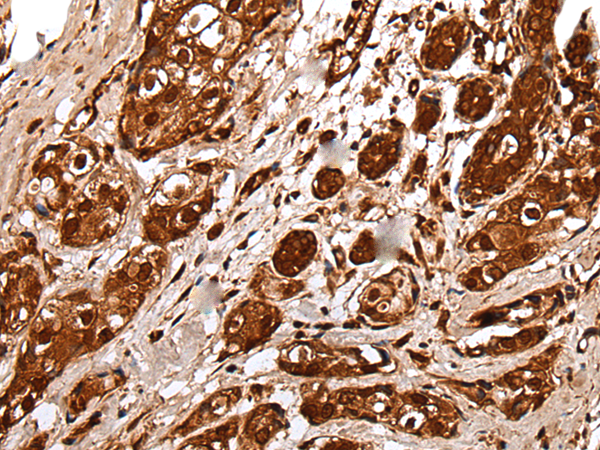

IHC (Immunohistochemisry)

(The image on the left is immunohistochemistry of paraffin-embedded Human breast cancer tissue using UBE2V1 Antibody at dilution 1/40, on the right is treated with fusion protein. (Original magnification: x200))